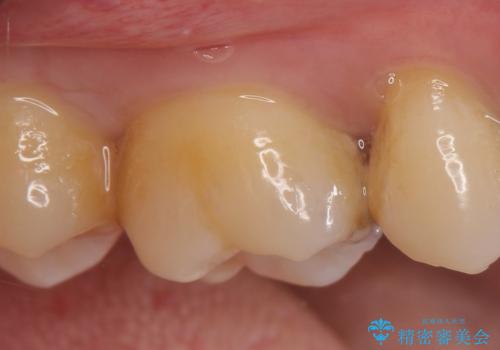

- 右上の奥歯で冷たいのもがしみるといらっしゃった方の症例です。

虫歯を除去後、セラミックインレーによる修復を行いました。